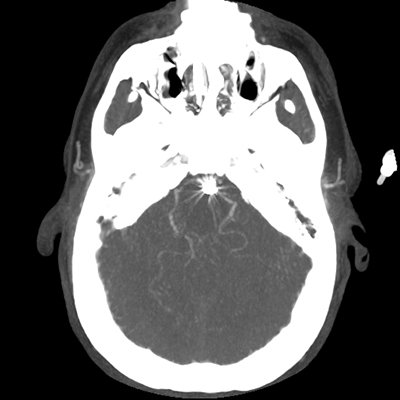

The patient goes down to CT. The following images are obtained. The subdural fluid collection is stable, as is the ventricular caliber.

Starting with the non-contrast head CT, we can appreciate that there's actually not much residual subarachnoid blood at all; it's essentially all resorbed already (and cleared through the EVD). The ventricular caliber is stable. With the CTA head (for convenience's sake, the MIPs were shown), it's subtle, but we can see that the PCAs on each side are not as smooth and regular. The right MCA, starting at the bifurcation, also becomes narrower. This is [radiographic] vasospasm. Now, looking at the CT perfusion-- specifically, the Tmax (MTT) map that were selected-- there's clearly some abnormality within the bilateral cerebellar hemispheres and occipital lobes. Not a lot, but it's there. Delving further into this map, we can appreciate that the areas of abnormality are mainly green, signifying that these areas have Tmax > 6 seconds. This is the threshold that is specific, not sensitive, for vasospasm.

Putting this all together, we have thus identified radiographic vasospasm with the vessel imaging, with perfusion abnormalities that are concordant with it. Does the area of vasospasm and hypoperfusion correlate with the patient's clinical exam?

Yes! It does. The patient had a decline in level of consciousness with diffuse loss of motor function. This does correlate to the basilar territory. (Alternatively, bilateral MCA vasospasm could also be responsible, reminding us that a decline in consciousness could technically be focal/multifocal.) Thus, we can say that this patient does have clinical vasospasm. Whether this will develop into irreversible DCI remains to be seen; at least, the non-contrast head CT and the other portions of the CT perfusion (not shown) currently don't [yet] suggest infarction.